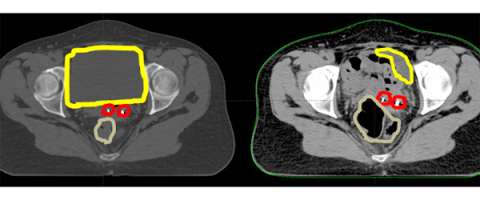

The simulation process when a patient is going to receive IMRT/IGRT takes an extra step (a bladder empty scan is done in addition to a bladder full one). The reason for this can be seen and explained through the following cartoons:

In these cartoons the yellow circle represents the bladder, the red oval represents the vagina, the brown circle represents the rectum, and the blue outline represents the area that will be treated with radiation. The first figure represents a typical example of the radiation field for 3D-conformal radiation. A large enough radiation field is used so we can ensure that all the targets are included with a generous margin. In treating with a larger margin organ motion (ie bladder/rectum being full vs empty) aren’t as relevant because the target will always fall within the radiation field.

So in this cartoon one can see that the target for radiation is really the upper vagina (red oval) and tissues around it and the radiation field in blue is just covering this area with a small margin extending into the bladder and rectum.

Because we are using smaller margins it is imperative that we understand how organ motion (ie rectal/bladder filling) moves the target so that we can ensure we are properly treating the intended target. To accomplish this we do the simulation with an empty rectum (ie making sure the patient has a bowel movement prior to simulation and is not constipated) and do a simulation with the bladder full and another one with the bladder empty. What this allows us to do is to see how the target moves based on your bladder filling. The target is contoured on both the bladder empty and the bladder full scans and is then fused together. This fused target volume gives us confidence that the target will fall within this volume on a daily basis.

Here is an axial CT scan slice of an actual patient with her bladder full on the left and her bladder empty on the right. You can see that with the bladder (yellow) empty that additional bowel falls within the pelvis and that the marker seeds (red) are in a different place (also in part due to increased air in the rectum (brown). This example demonstrates the importance of daily image guidance and making sure that your bladder is consistently full during the course of your treatment.